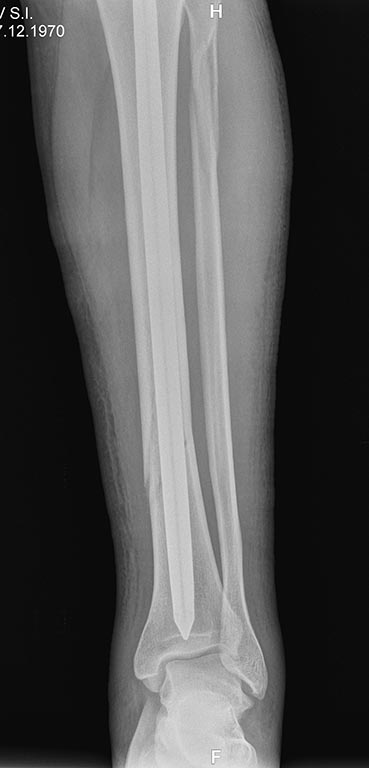

Уважаемые коллеги, по просьбе официального представителя компании FIXION в Украине -представляем вашему вниманию клинический случай перелома 42 A1

(для нас этот случай вызвал интерес в связи с достаточно низким расположением линии перелома большеберцовой кости и отсутствием у нас опыта применения FIXION).

Пациент 1970г.р., соматически здоров. Непрямой механизм травмы, низкая энергия. Операция на 7е сутки.

Интраоперационно использовали дистрактор.

Возникали сомнения в достижении стабильной фиксации дистального фрагмента без блокировки винтами. Итог - синтез стабильный, дозированная нагрузка с первого дня. Результаты представлены на рентгенограммах. С уважением, Максим Канзюба.